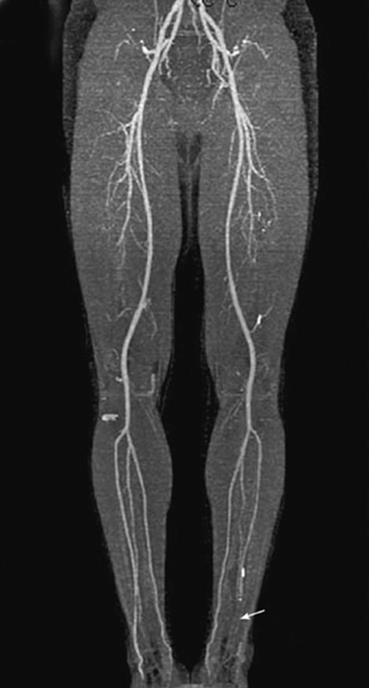

The basic anatomy is fairly consistent (see Figure 19-1). Collateralization is crucial for patients with atherosclerotic disease, as it provides continued blood supply and also serves as a “detour” during acute occlusion. It is most commonly seen around major branch points: the external iliac filling through the pelvis (from the internal iliac artery), the superficial femoral artery reconstituting via the profunda femoris artery, and the foot filling through patent tibial vessels.

Figure 19-1. Arterial circulation of the lower extremities. The left anterior tibial artery (arrow) is noted to be diseased. (Reproduced with permission from Brunicardi FC, Andersen DK, Billiar TR, et al. Schwartz’s Principles of Surgery. 9th ed. New York: McGraw-Hill; 2010 [Figure 23-59].)